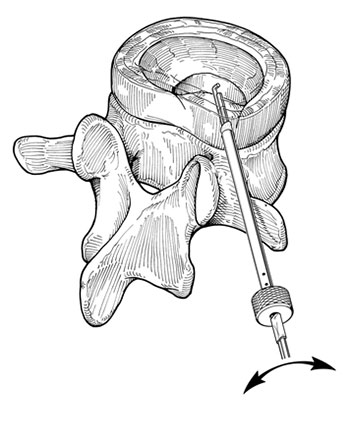

Após a introdução do fio guia procede-se com o dilatador, seguido da cânula, para finalmente poder introduzir o microressector, aparelho com o qual é realizada a ressecção do conteúdo do disco (Fig 5 a-e).

Fig. 5a

Fig. 5b

Fig. 5c